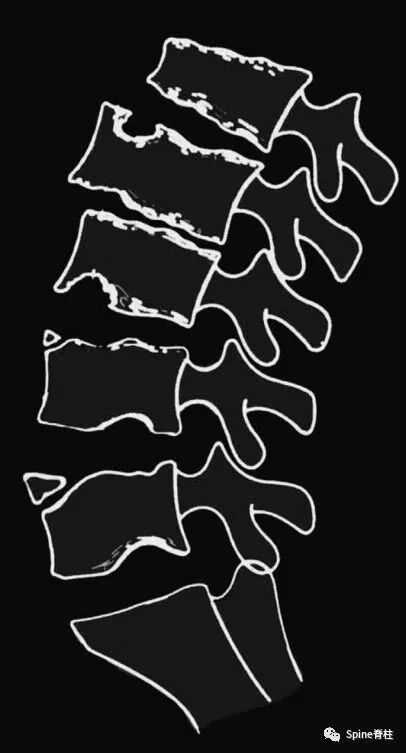

典型休门氏病后凸畸形

典型休门氏病。A:胸椎型;B:胸腰椎型 (PMID: 26536439)